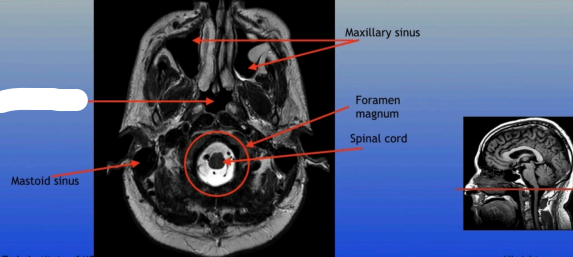

Mastoid Sinus

Maxillary Sinus

Foramen Magnum

Spinal Cord